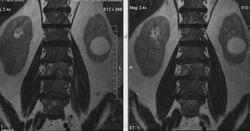

Метастазы рака простаты, кроме измений в позвонках видна сама первичная опухоль и лимфатические узлы (общий и наружный подвздошные слева, ещё один в левой подвздошной ямке).

После добавления томограмм исследования органов малого таза картина стала ещё печальнее...

Да, запустил пациент. До этого были проблемы с мочеиспусканием, рези, болезненность. Лечился самостоятельно от простатита, отмечал временное улучшение.